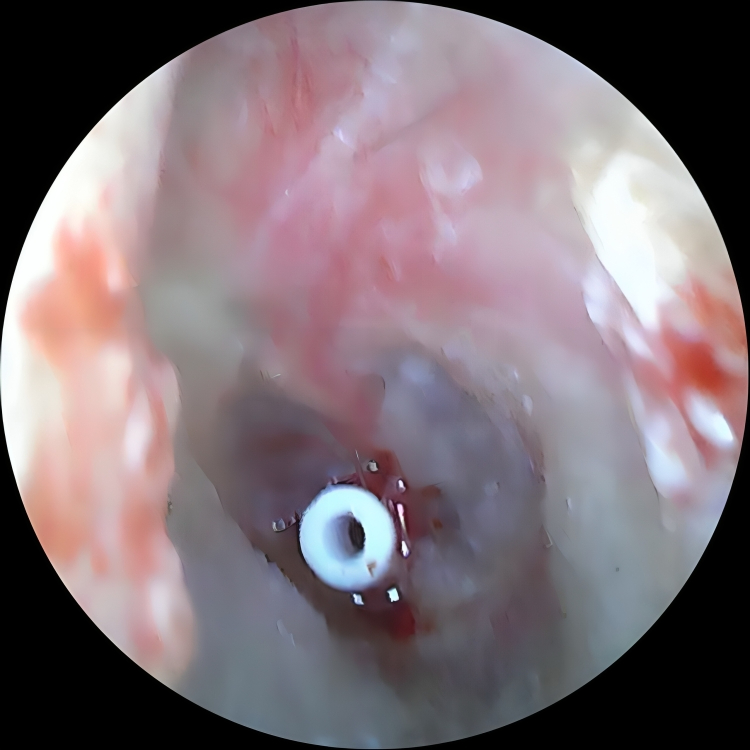

Read MoreAdvanced camera-based examination for accurate diagnosis of ENT concerns.

Read MoreSafe, quick procedures performed for common ear, nose and throat problems.

Comprehensive care for ear infections and hearing loss, including Tympanoplasty, Mastoidectomy, Ossiculoplasty and Stapedotomy/Stapedectomy for improved hearing outcomes.

He is skilled in endoscopic evaluations, minimally invasive ENT procedures, vertigo assessment and advanced ear - nose - throat care, ensuring precise and patient-friendly treatment.